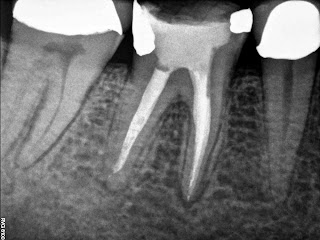

| Final |